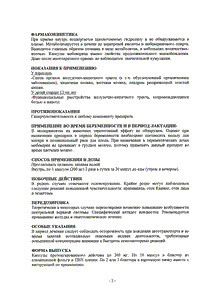

Фармакокинетика

Всасывание

Мебеверин быстро и полностью всасывается после приема внутрь. Лекарственная форма модифицированного высвобождения позволяет использовать схему дозирования 2 раза/сут.

Распределение

При повторном приеме препарата значительной кумуляции не происходит.

Метаболизм

Мебеверина гидрохлорид в основном метаболизируется эстеразами, которые на первом этапе расщепляют эфир на вератровую кислоту и спирт мебеверина. Основным метаболитом, циркулирующим в плазме, является деметилированная карбоновая кислота. T1/2 в равновесном состоянии деметилированной карбоновой кислоты составляет приблизительно 5.77 ч. При многократном приеме в дозе 200 мг 2 раза/сут Cmax деметилированной карбоновой кислоты в крови составляет 804 нг/мл, Tmax - около 3 ч.

Среднее значение относительной биодоступности препарата в капсуле с модифицированным высвобождением составляет 97%.

Выведение

Мебеверин в неизмененном виде не выводится из организма, он полностью метаболизируется; его метаболиты практически полностью выводятся из организма. Вератровая кислота выводится почками. Спирт мебеверина также выводится почками, частично в виде карбоновой кислоты и частично в виде деметилированной карбоновой кислоты.

Форма выпуска

Капсулы пролонгированного действия твердые желатиновые, размер №1, непрозрачные, белого цвета, с маркировкой "245" на корпусе капсулы; содержимое капсул - белые или почти белые гранулы.

| 1 капс. | |

| мебеверина гидрохлорид | 200 мг |

Вспомогательные вещества: магния стеарат - 13.1 мг, метилметакрилата и этилакрилата сополимер [1:2] - 10.4 мг, тальк - 4.9 мг, гипромеллоза - 0.1 мг, метакриловой кислоты и этилакрилата сополимер [1:1] - 15.2 мг, триацетин - 2.9 мг.

Состав оболочки капсулы: желатин - 75.9 мг, титана диоксид (Е171) - 1.5 мг.

Состав чернил: шеллак (Е904), пропиленгликоль, аммиак водный, калия гидроксид, краситель железа оксид черный (Е172).